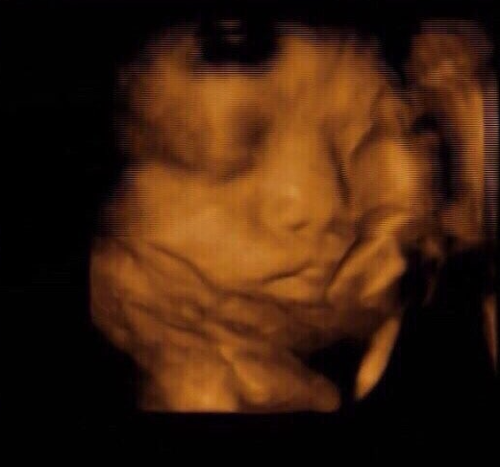

임신 23주.

“아기가 역아네요.

32주 넘어서도 이러면, 제왕절개도 고려해 보세요.”

그날 이후 나는 매일 밤 배에 손을 얹고 말했다.

“사랑아, 제발 한 번만 돌아줘.

엄마는 자연스럽게 너를 안고 싶어.”

그래도 사랑이는 꿈쩍도 하지 않았다.

세상에 나오기도 전에,

자신의 자리를 지키겠다는 듯.

그 모습이 고집스러웠다.

32주, 34주, 36주

끝까지 역아 자세였던 사랑이.